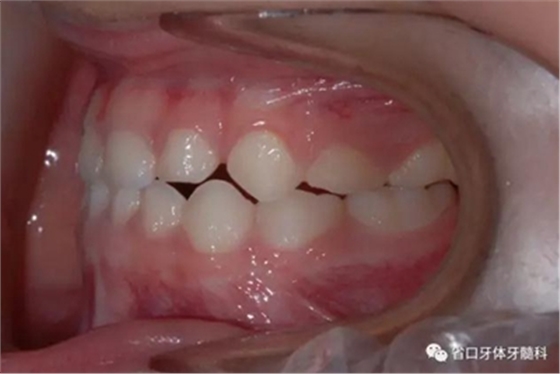

圖4 正面牙相(2015年1月)

圖7 上頜牙相